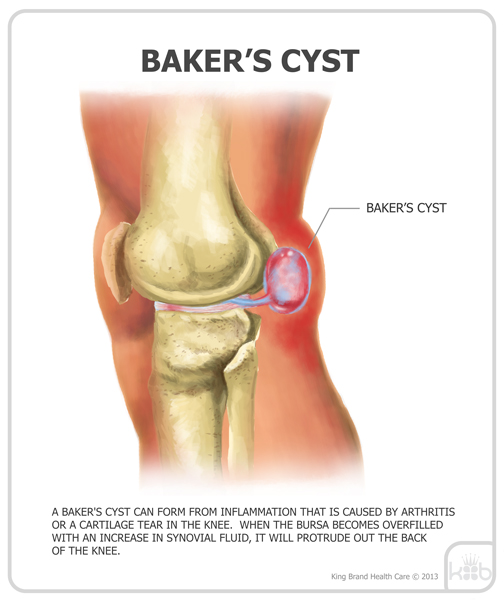

Фото и диагностика кисты Бейкера